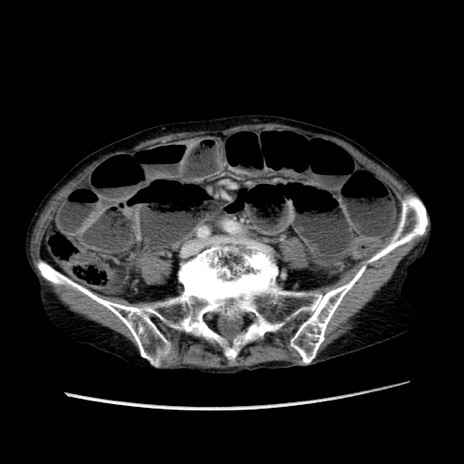

冠状断像

【症例】80歳代女性

【主訴】胸のつかえ感

【現病歴】約9時間前に食後から胸のつかえた感じあり、嘔吐あり、来院。

【既往歴】胃癌(全摘)、胆摘、虫垂炎

【身体所見】心窩部に圧痛あり、反跳痛なし。

【データ】WBC 5700、CRP 0.05